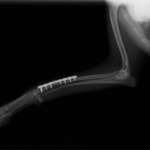

症例:交通事故による椎体脱臼

柴犬:9歳、避妊雌

交通事故直後、胸腰部に激しい疼痛、両後肢に完全麻痺を認め、シェフシェリントン徴候を呈していました。レントゲン検査において、第11-12胸椎間の脱臼が認められました。

脊髄の減圧、脊柱管の再構築・安定化を目的に、片側椎弓切除術およびMatrixMANDIBLE Plateによる椎体固定を実施しました。

隣接椎体を架橋するようにプレートを設置しました。

術後レントゲン写真